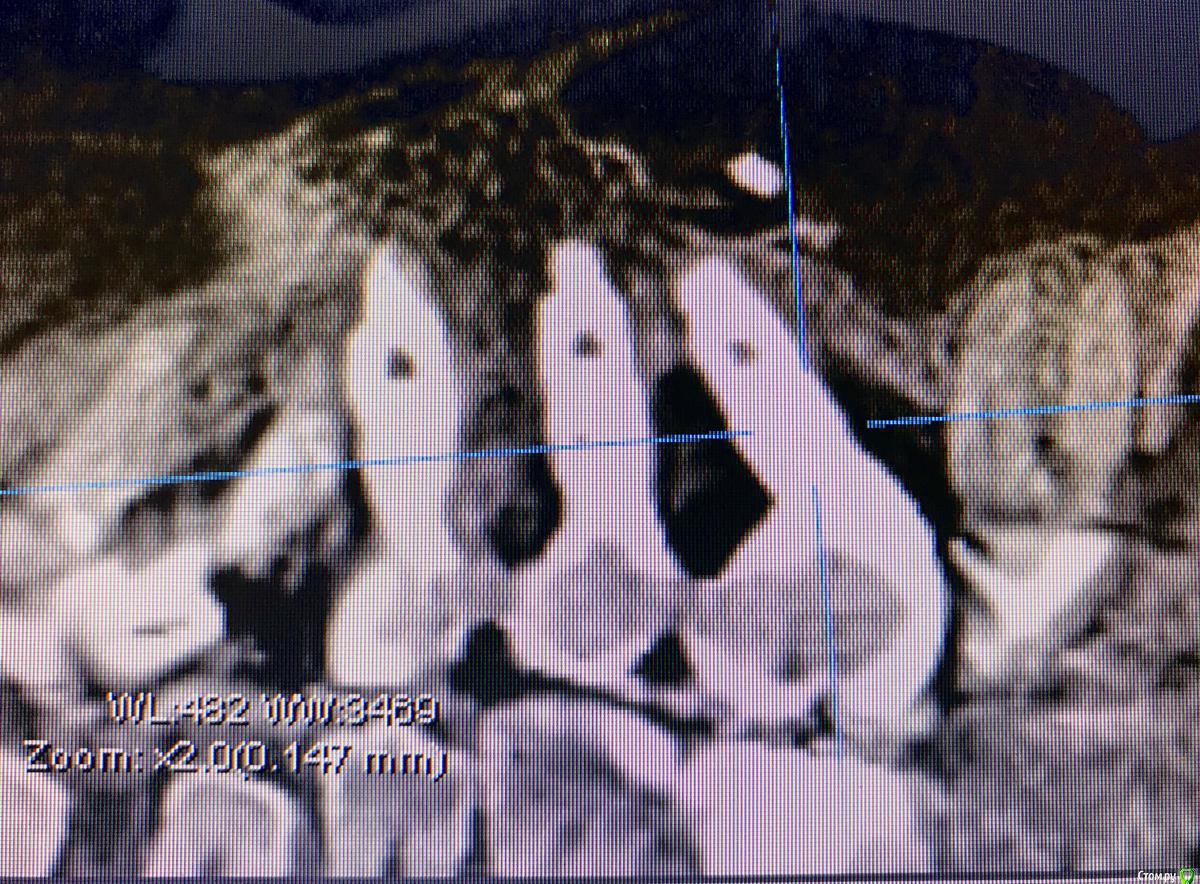

DenisV Опубликовано 21 марта, 2018 Поделиться Опубликовано 21 марта, 2018 Уважаемые коллеги планируется удаление и установка имплантата 3.8 10 dentium можно ли будет обойтись без костной и тканевой аугментации? Ссылка на комментарий

DenisV Опубликовано 21 марта, 2018 Автор Поделиться Опубликовано 21 марта, 2018 Уважаемые коллеги планируется удаление и установка имплантата 3.8 10 dentium можно ли будет обойтись без костной и тканевой аугментации? Ссылка на комментарий

колесников Опубликовано 21 марта, 2018 Поделиться Опубликовано 21 марта, 2018 (изменено) Чтобы отвертка не уперлась в режущий край,ставить лучше более вертикально,Апекс в этом случае будет близко к вестибулярной компактной пластинке ,после нагрузки может быть окончатся резорбция. Мне кажется, 10 мм с заглублением, самое то. Изменено 21 марта, 2018 пользователем колесников 1 Ссылка на комментарий